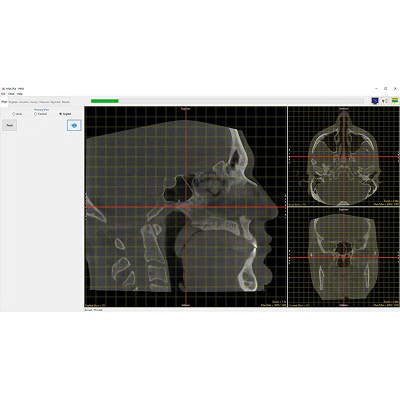

Align

The HNA app opens to the first function tab, which is the Align tab. This provides a way to realign the volume if it wasn’t lined up precisely as desired during the scan procedure.